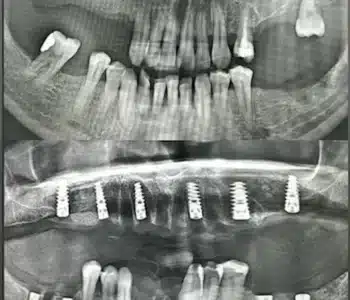

Dr. Seden Aksu is a specialist in modern implantology and surgical dentistry with extensive experience in the management of complex clinical cases. In her practice, she applies comprehensive surgical planning, minimally invasive techniques, and advanced regenerative technologies aimed at restoring both the function of the dentoalveolar system and the aesthetics of the smile. Dr. Aksu has significant experience in performing implant procedures, bone augmentation, and periodontal surgery, including the treatment of patients with severe bone loss. The primary goal of her work is to achieve stable, long-term outcomes in implant rehabilitation and the restoration of oral tissue health.